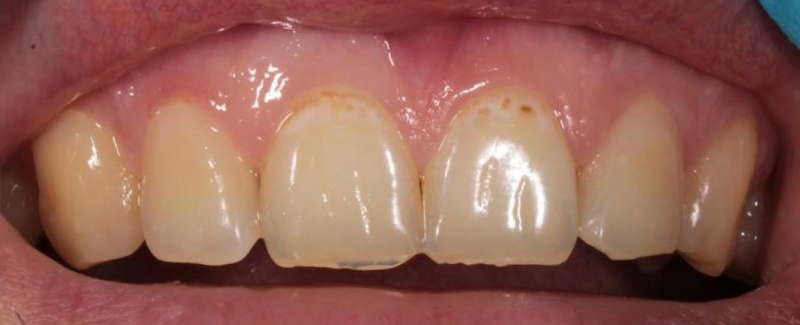

На странице представлено портфолио стоматологий Санкт-Петербурга с работами до и после профессиональной чистки зубов. В нашем портфолио собраны разные клинические случаи: от удаления незначительного налета до снятия массивного поддесневого камня. Здесь вы можете увидеть, как возвращается естественный цвет и внешний вид зубов после процедуры. Изучите результаты до и после чистки зубов, чтобы увидеть реальный эффект и выбрать клинику в Санкт-Петербурге, где профессиональная гигиена поможет вернуть зубам здоровый вид.